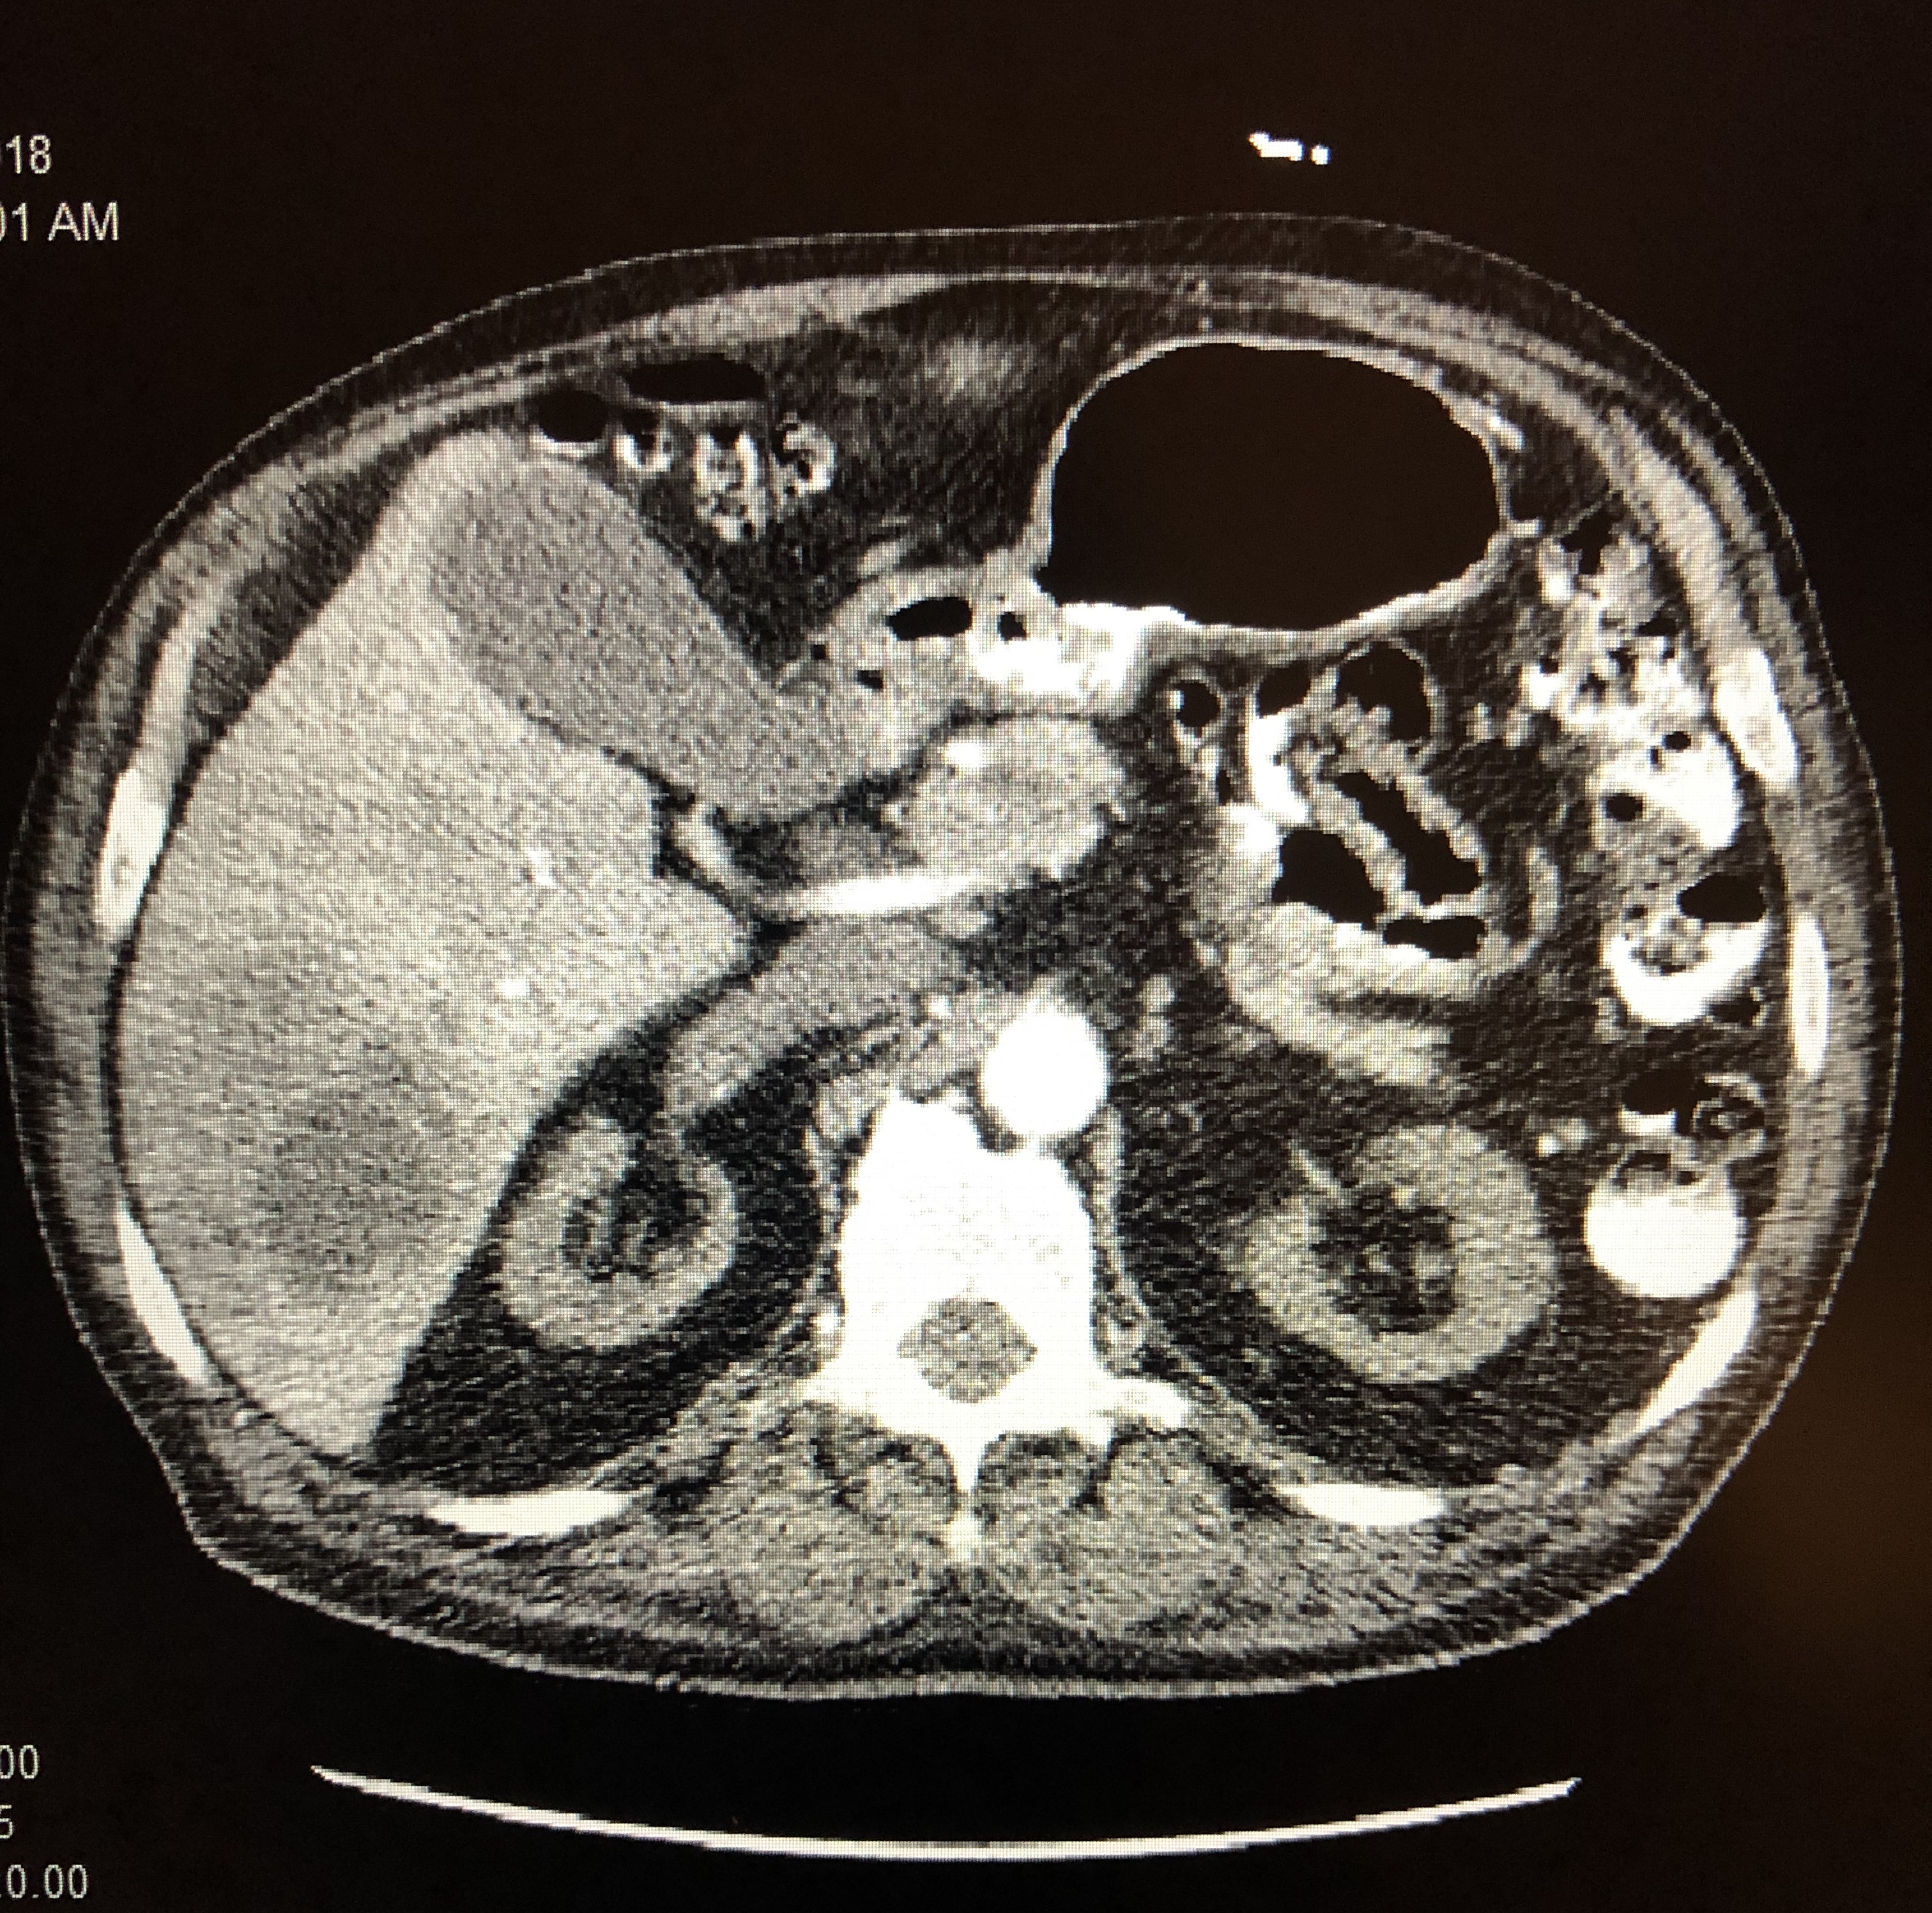

A subsequent CT scan of the chest, abdomen, and pelvis with contrast demonstrated a lung abscess and a 9.0-cm, multilocular, rim-enhancing liver abscess (Figure 2).

Figure 2. CT scan with contrast showing a multilocular, rim-enhancing liver abscess.